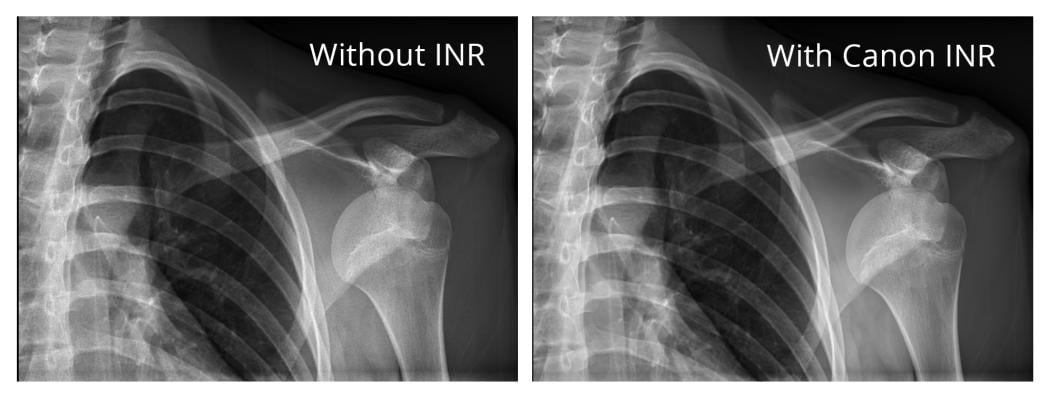

The authors note that ionizing radiation is the basis for the production of diagnostic X-rays, however it has long been proven to increase the risk of cancer. The white paper evaluates the capabilities of Canon Intelligent NR and its deep learning neural network (DLNN) software in relation to standard and decreased dose pediatric digital radiographs at Dayton Children’s Hospital, Dayton, Ohio.

According to Dr. Elizabeth Ey, chief radiologist and radiation safety officer at Dayton Children’s Hospital, “The Canon DR system with the Intelligent Noise Reduction has produced images with lower noise content at a lower dose with no visible loss in image quality. This has allowed us to use doses that are 50% less than what we had been using in that room.”

The pediatric radiography study data suggests that Canon DR’s deep learning Intelligent NR software is effective and assists radiologists in diagnostic imaging.The Intelligent NR technology is compatible with Canon’s previously introduced CXDI flat panel detector (FPD) series. Compatible models are: CXDI-710C Wireless, 810C Wireless, 410C Wireless, 720C Wireless, 820C Wireless, 420C Wireless, and 420C Fixed.